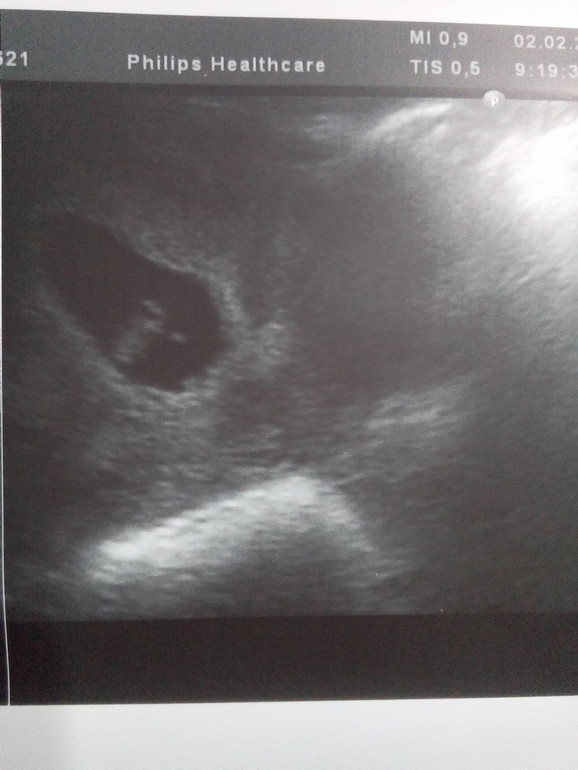

В 7+4 ( фото по животу):

ПЯ 30 мм, КТР 15 мм, ЧСС 164 уд/ мин, ЖМ 5 мм, плацента в дне матке.